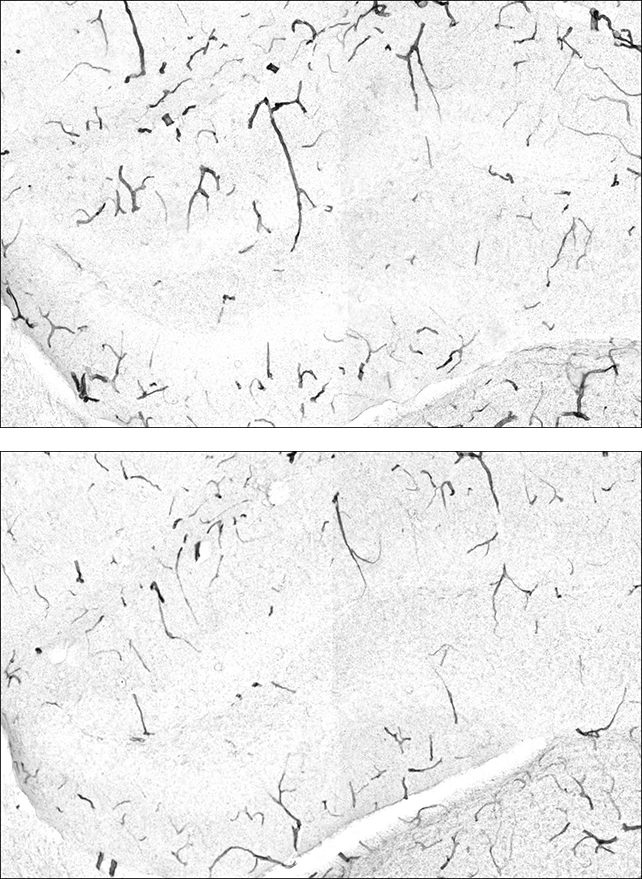

That protein – more succinctly referred to as GPLD1 – strengthens the barrier that guards the brain against all sorts of unwelcome visitors within our blood, protecting against inflammation and subsequent cognitive decline.

A recent study led by a team from the University of California, San Francisco (UCSF), has identified a connection between GPLD1 and TNAP (tissue-nonspecific alkaline phosphatase) – an enzyme that typically ensures the barrier remains permeable when conditions get stressful.

Over time, however, TNAP accumulates within the blood-brain barrier’s cells, impairing their functionality. The study found GPLD1 ‘prunes’ TNAP from tissue, strengthening the brain’s protection against inflammation.

Young mice that were genetically engineered to have more TNAP in their blood-brain barrier showed cognitive decline consistent with older mice.

When older mice were genetically engineered to have less TNAP than normal, leaks were reduced in the blood-brain barrier, inflammation went down, and cognitive abilities improved.

In mice with a model of Alzheimer’s disease, increased levels of GPLD1 or reduced levels of TNAP were both associated with fewer harmful clumps of the amyloid beta protein that are hallmarks of Alzheimer’s, another positive sign.